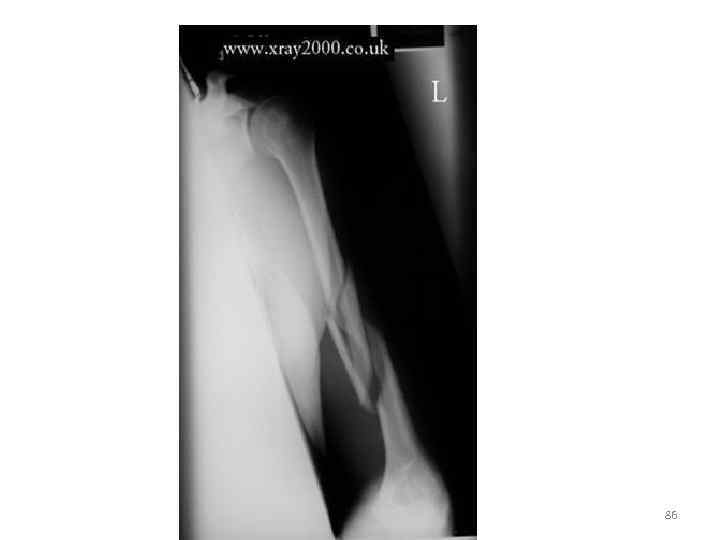

86

• На рентгенограмме левой плечевой кости в задней атипичной проекции определяется: спиралевидный оскольчатый перелом на границе средней и нижней третей диафиза плечевой кости со смещением отломков по ширине на 1/3 диаметра кости кнаружи, с образованием крупного клиновидной формы осколка 87